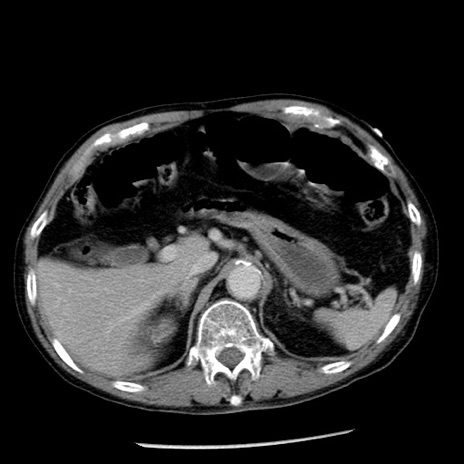

症例26(横断像)

【症例】80歳代男性

【主訴】嘔吐

【現病歴】昨晩2回嘔吐あり、今朝になっても嘔吐あり。来院。

【既往歴】胃潰瘍

【身体所見】意識清明、BT 37.6℃、BP 166/95mmHg、HR 100bpm、SpO2 97%、腹部:平坦・軟、腸蠕動音聴取良好、圧痛なし。

【データ】WBC 21900、CRP 1.46